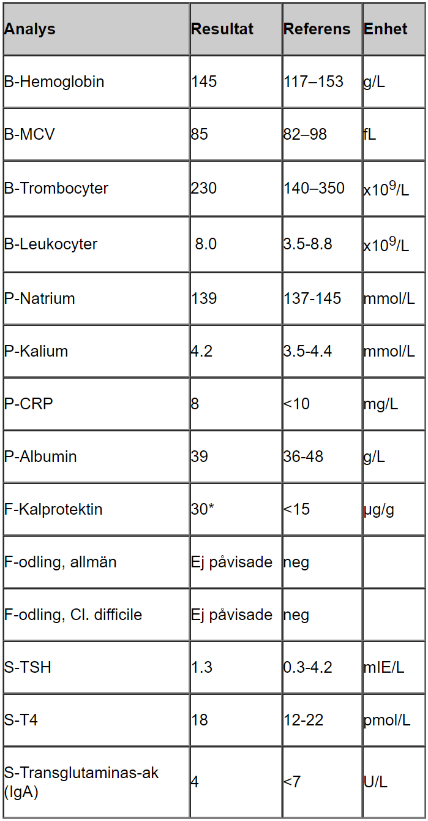

Tolka proverna

- B-hemoglobin, MCV, ferritin lågt vilket tyder på inflammation/blödning, eventuellt problem med näringsupptag

- Trombocyter högt som kompensation för blödning

- CRP lite högt tyder på låggradig inflammation

- Albumin lågt kan tyda på inflammation (omvänd markör)

- F-Kalprotektin högt tyder på IBD

- F-hemoglobin tyder på att det pågår blödning i tarmen, hon har inte uppmärksammat det själv vilket tyder på blödning något mer proximalt i tarmen